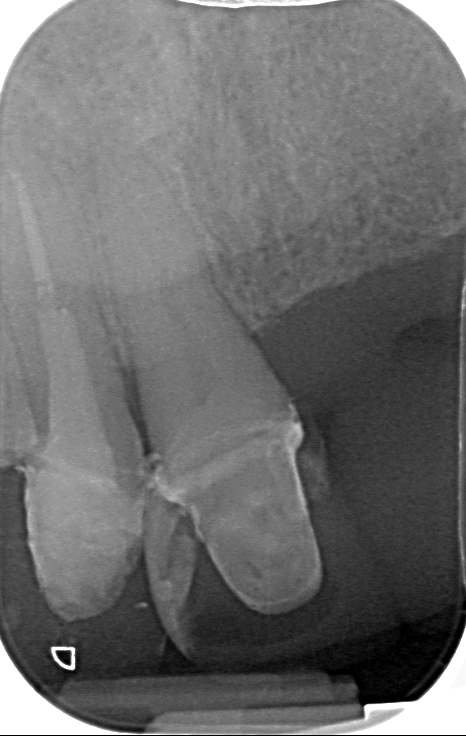

Περιστατικό 4

Αφαίρεση χυτού ενδορριζικού άξονα και επανάληψη κακότεχνης ενδοδοντικής θεραπείας σε άνω πλάγιο τομέα. Το δοντι αποκαταστάθηκε με νέο άξονα υαλονημάτων.